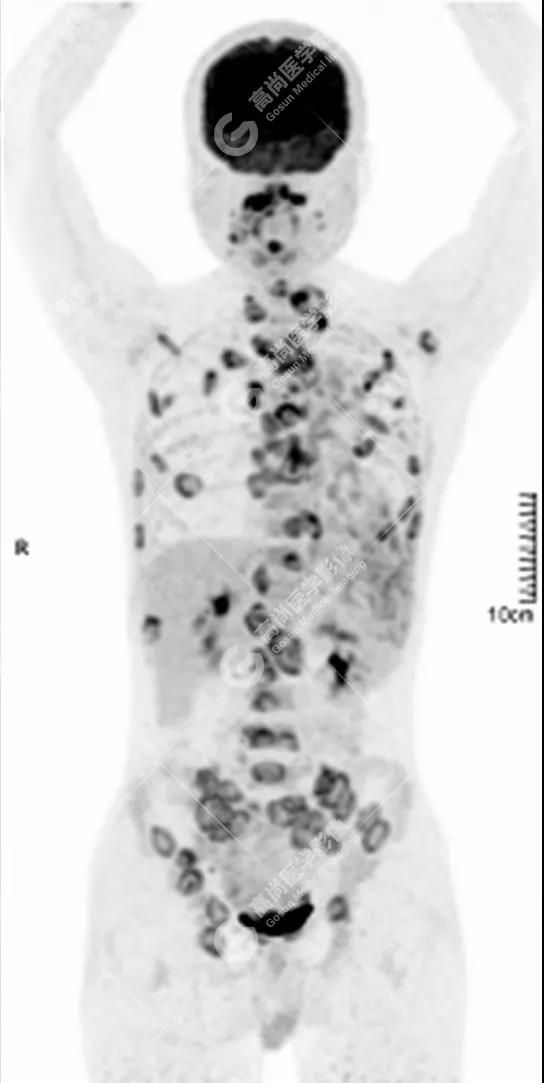

PET/CT全身圖

全身多處骨質(zhì)破壞,代謝不均性增高

全身多發(fā)高代謝腫大淋巴結(jié),中央代謝缺損

雙肺、左側(cè)胸膜多發(fā)結(jié)節(jié)影,全身多處骨質(zhì)破壞,全身多發(fā)淋巴結(jié)腫大,代謝攝取不均勻性增高。

1.全身未找到原發(fā)腫瘤病灶;

2.全身多系統(tǒng)、多形態(tài)、多發(fā)病灶(肺部、胸膜、淋巴結(jié)、骨),18F-FDG攝取不均性增高;

特征:肺部病灶簇狀分布,上葉尖段及下葉背段為著;腫大淋巴結(jié)分布不對稱,無融合、中央有壞死改變,與淋巴瘤、轉(zhuǎn)移瘤等有一定的鑒別診斷意義;

診斷意見:綜合考慮感染性病變(結(jié)核),建議相關(guān)實(shí)驗(yàn)室檢查。